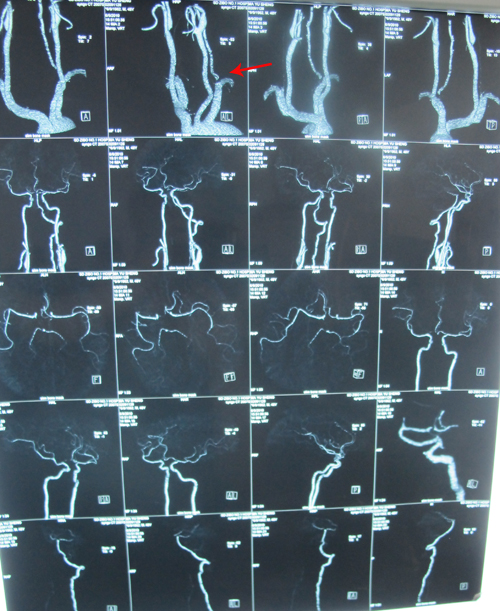

全脑血管造影:右颈内动脉、右椎动脉起始部分别狭窄95%,90%,右椎动脉颅内段未显影。

颈部血管超声:双侧颈动脉硬化斑块形成,右侧颈动脉狭窄,右侧椎动脉狭窄供血不足并高阻。